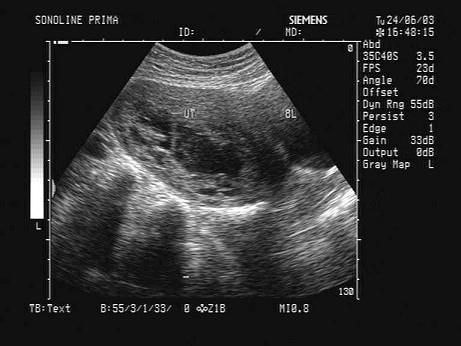

问题 女,26岁,早孕药流后阴道流血就诊,超声声像图如下,最可能的诊断为?(?)

选项 A.正常早孕 B.先兆流产 C.胎盘置入 D.稽留流产 E.不全流产

答案 D